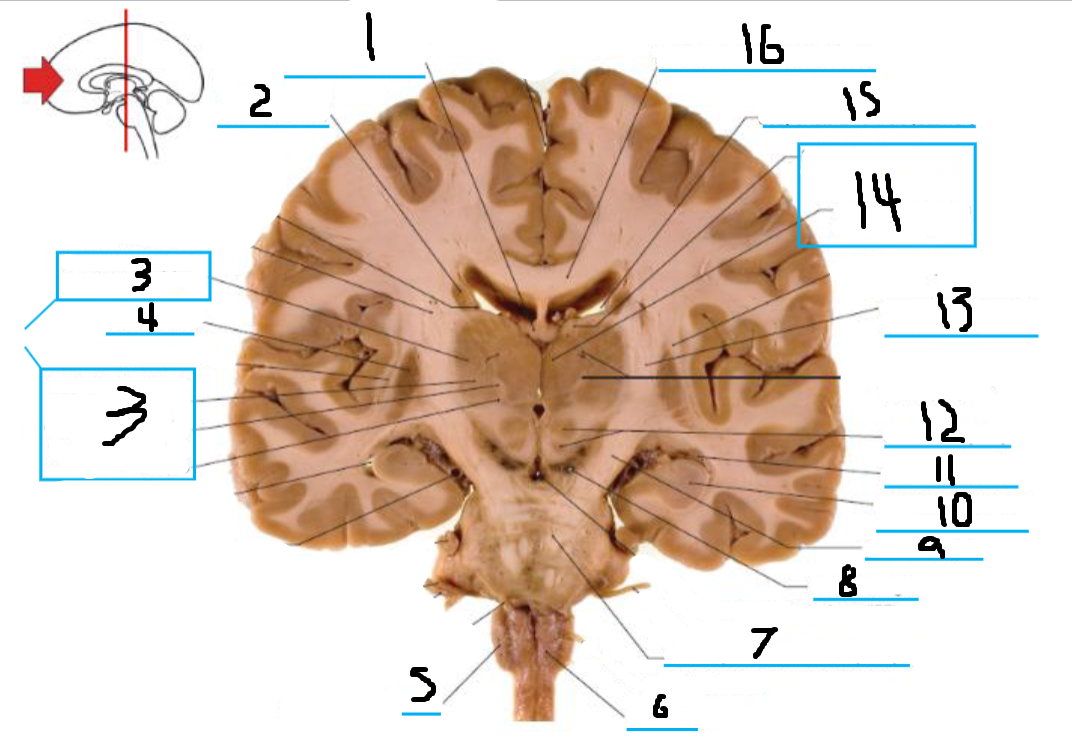

#1 is the:

Fornix

#2 is the:

Caudate

#3 and #14 is the:

Thalamus

#4 is the:

Putamen

#5 is the:

Olive

#6 is the:

Pyramid

#7 is the:

Basilar Pons

#8 is the:

Substantia Nigra

#9 is the:

Crus Cerebri

#10 is the:

Hippocampus

#11 is the:

#12 is the:

Red Nucleus

#13 is the:

Internal Capsule

#15 is the:

Lateral Ventricle

#16 is the:

Corpus Callosum